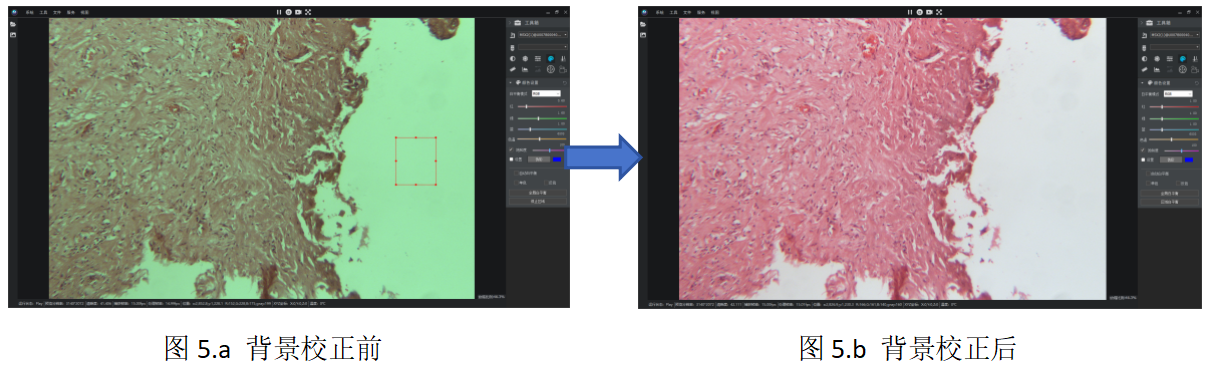

ĶÉĶÚī@ÎĸįRšâÔ´ÅcĪāCÄŦÕJÔOÖÃĩIJîŽŖŦÜŧūŗÉĪņąŗž°ŋÉÄÜŗöŦFÆĢÉĢŖ¨Čį°lüSĄĸˇēË{ĩČŖŠŖŦČįD1ËųĘžĄŖ´Ëîî}ŲĶÚÕũŗŖŦFĪķŖŦŋÉͨß^ÜŧūČÖÚ¤žßŋėËŲĐŖÕũĄŖ